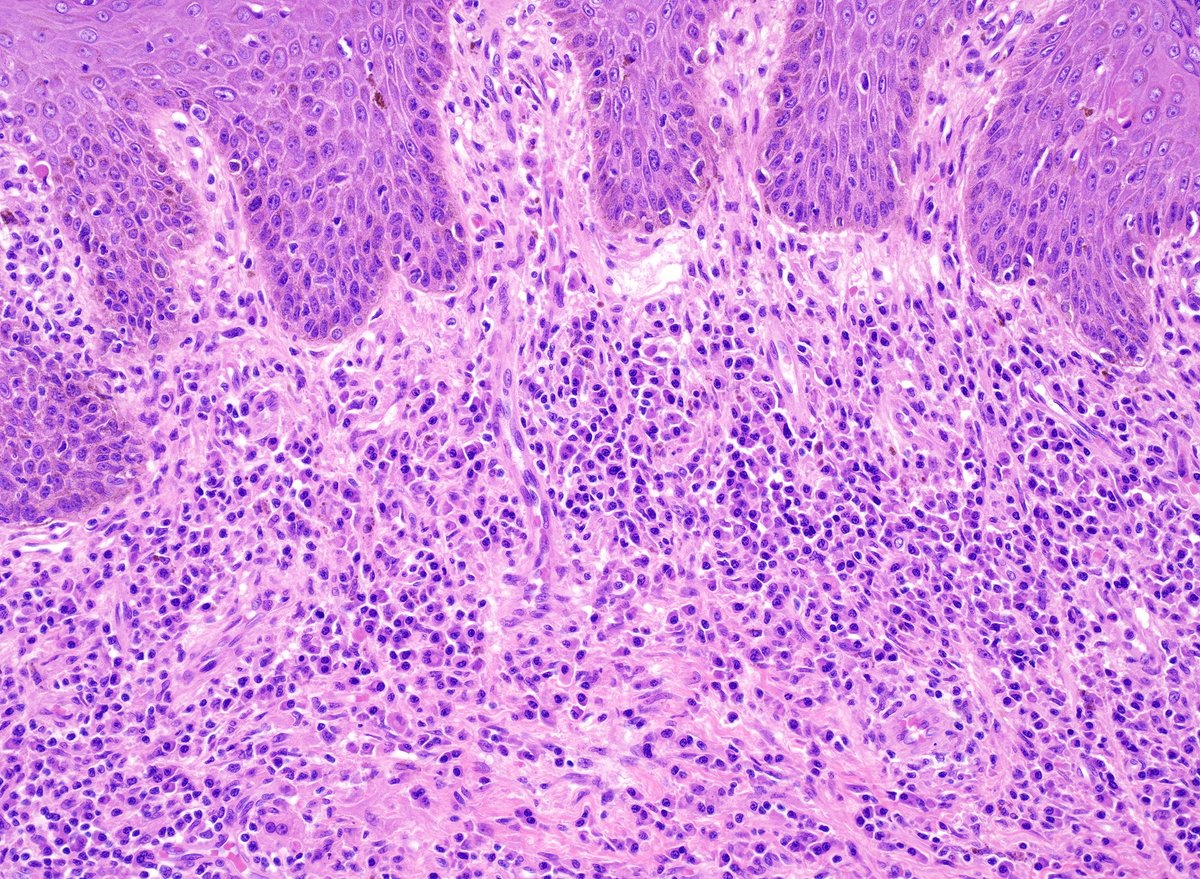

Adult male with a large ulcerated and indurated lesion on foreskin. What would you do next? Additional images and diagnosis will be posted later. #gupath

WebPathology's tweet image. Adult male with a large ulcerated and indurated lesion on foreskin. What would you do next? Additional images and diagnosis will be posted later. #gupath